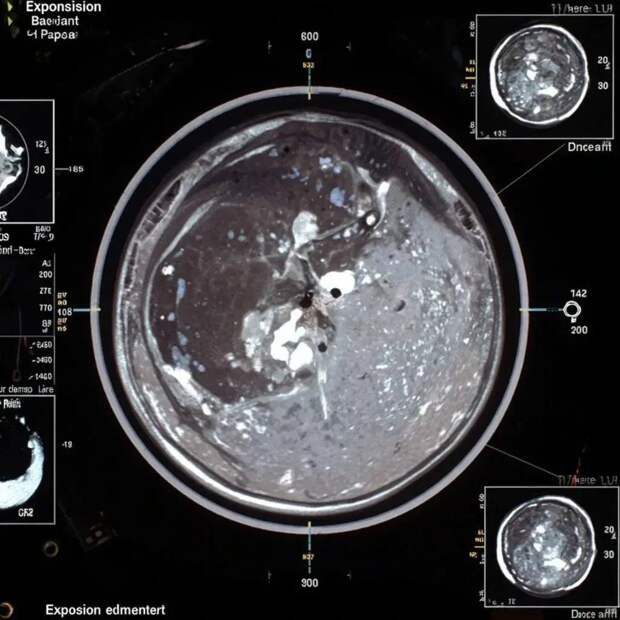

Магнитно-резонансная томография (МРТ) глазных орбит представляет собой высокоинформативное неинвазивное исследование структур глаза и окружающих тканей. При необходимости уточнения патологических изменений может быть назначена процедура с введением контрастного вещества.

Контрастирование позволяет повысить точность диагностики за счет улучшения визуализации сосудистой сети и мягких тканей, что существенно повышает диагностическую ценность исследования при опухолях, кровоизлияниях и инфекционных процессах.